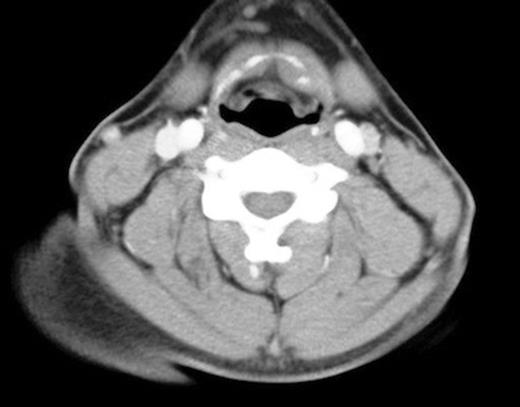

The mechanism of injury and examination findings raised a clinical suspicion of a severe traumatic insult, and he was admitted on the ENT ward to undergo an urgent CT scan of the neck. This demonstrated dislocation of the symphysis between the left medial greater cornu and left body of the hyoid (figure 1).

Dislocation of the symphysis between the left greater cornu and the body of the hyoid bone

There was minor asymmetry of the valeculla and the left vocal cord (figure 2), but otherwise no significant airway compression. Management involved conservative treatment only with appropriate analgesia. On examination two weeks later, all his symptoms had settled. Repeat flexible nasal endoscopy showed only soft tissue swelling and minor asymmetry of the left valeculla.